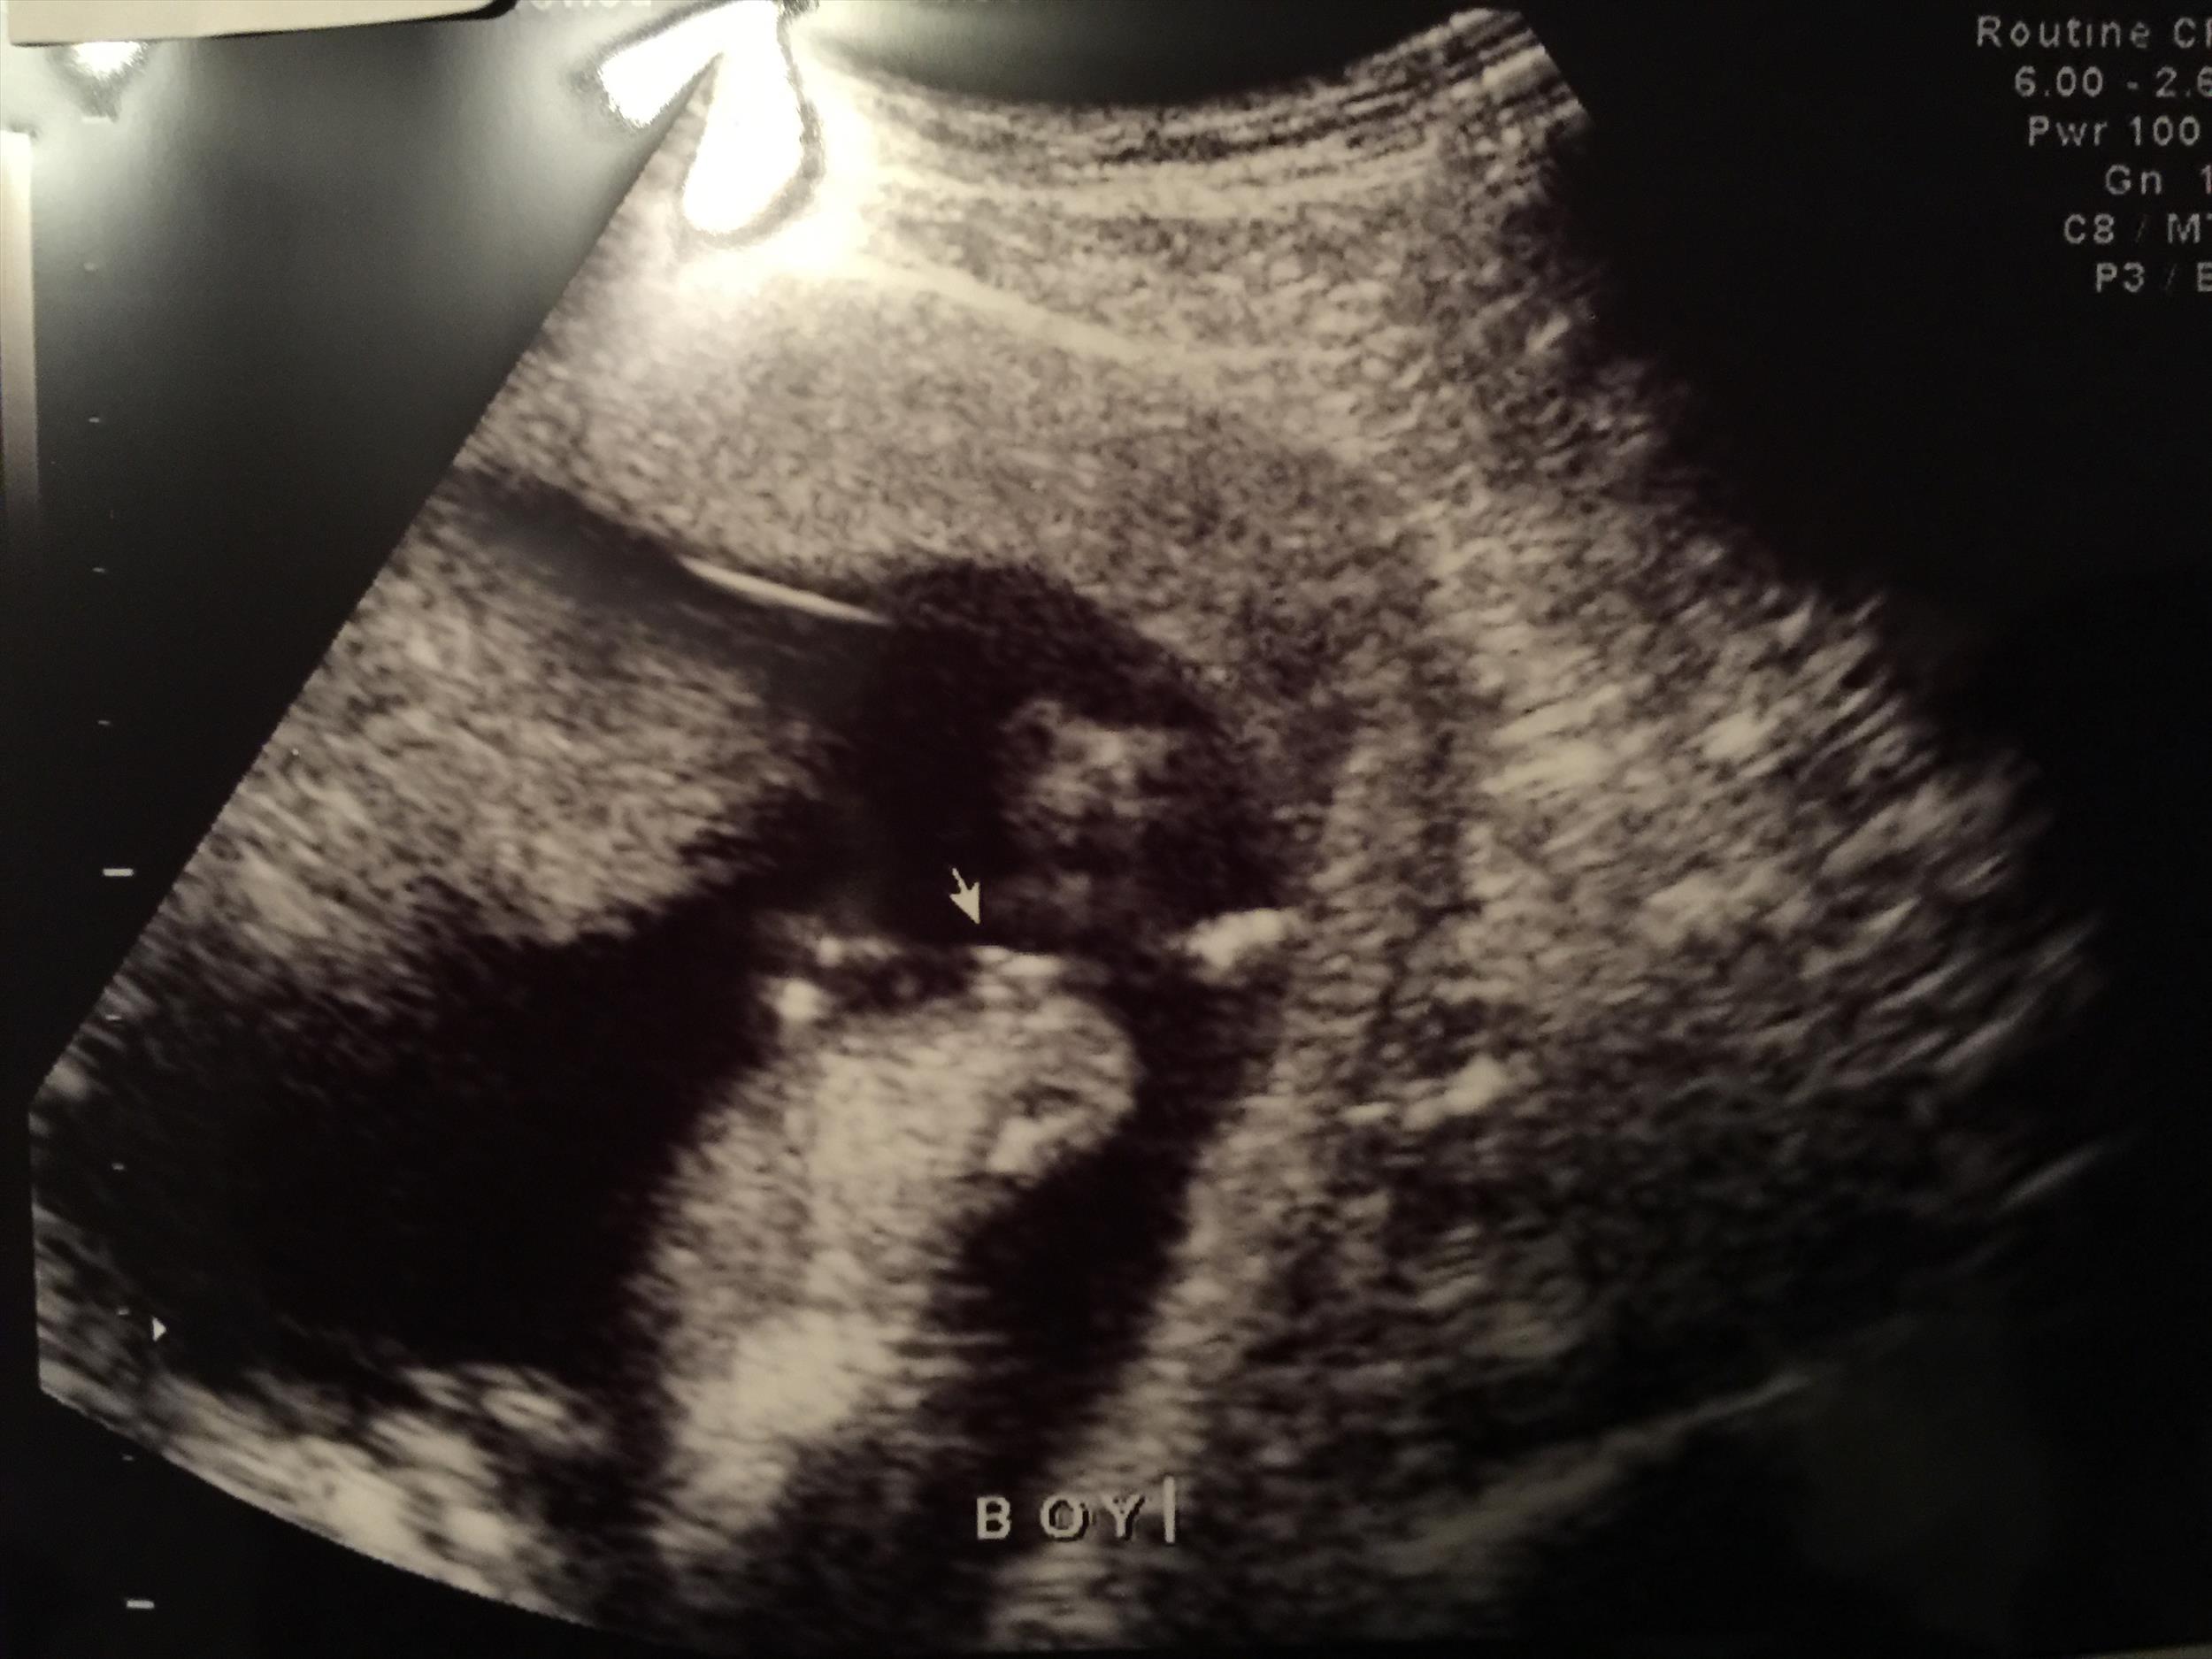

Just got a gender ultrasound at 13wk5d. Sonographer says "boy" but I wanted to make sure she didn't make a mistake. Please let me know if it's pretty obvious in these pictures. Thanks so much :)

Attachment 29090Attachment 29091Attachment 29092Attachment 29093Attachment 29094